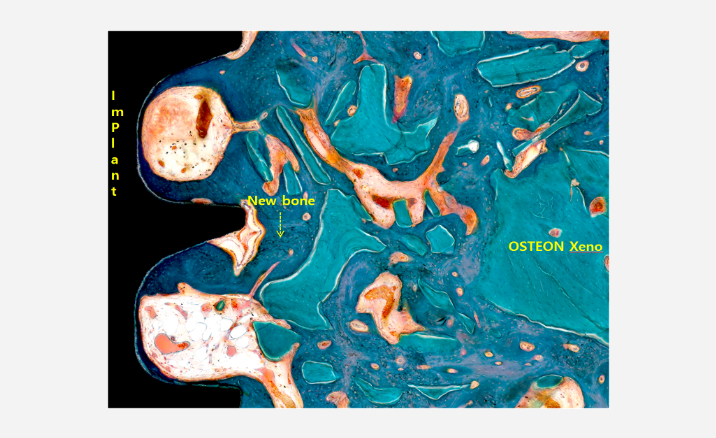

분석 예시

2D & 3D 이미지 및 정량분석

Implant 체결 구조 분석

Resin 제작

비탈회

(레진제작)

Implant